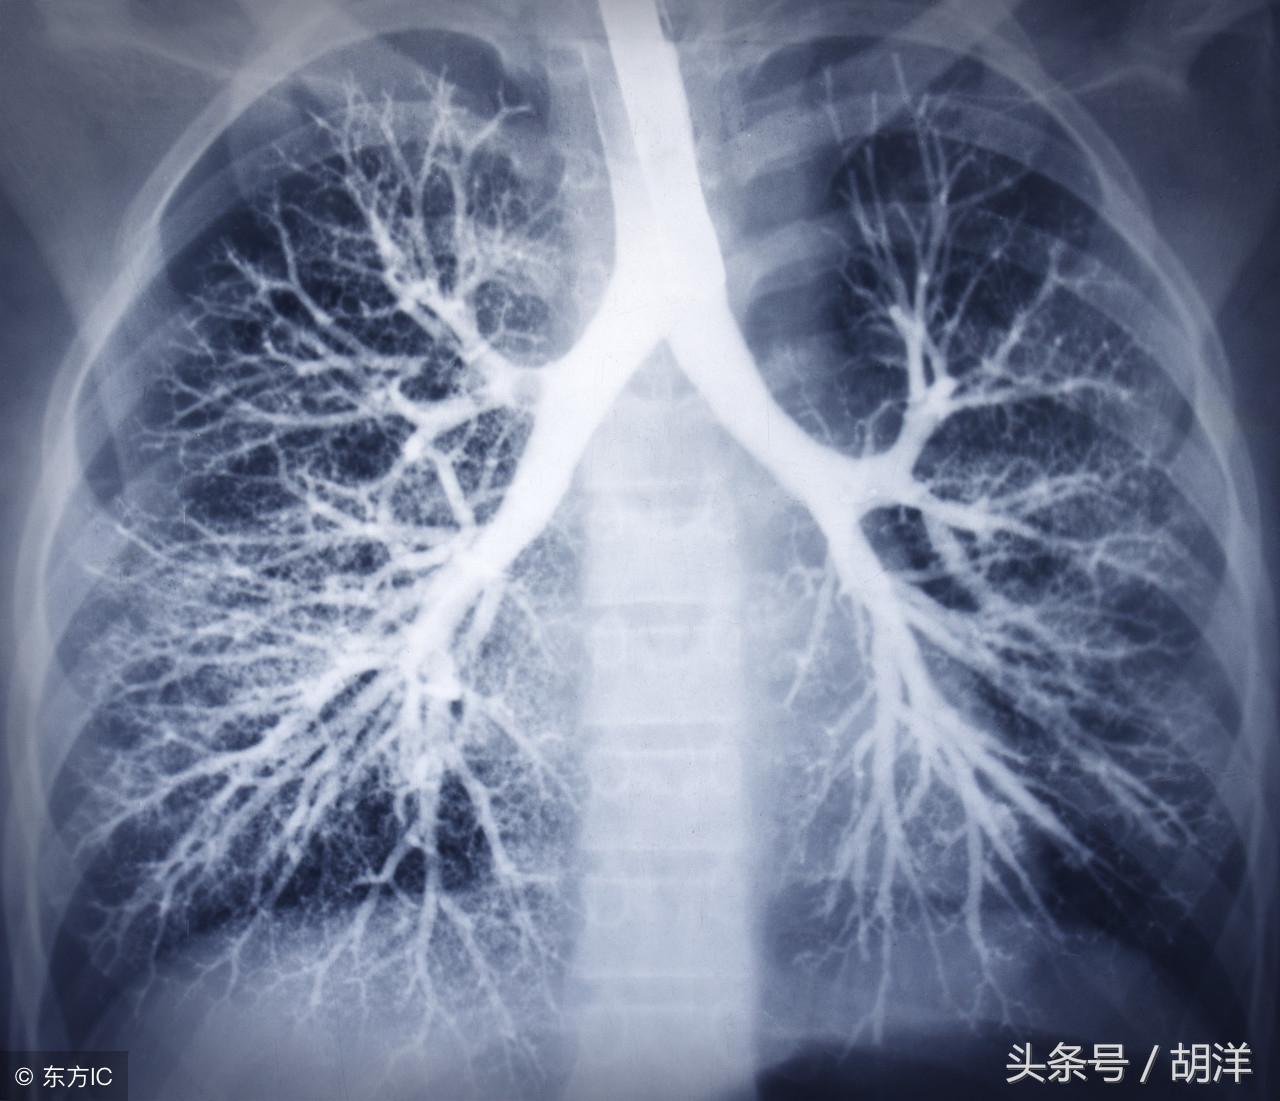

咳血又称咯血,是呼吸科一个比较严重的症状,由于其可能提示肺部肿瘤等严重疾病而受到重视,但事实上在引起咯血的病因中,肺部恶性肿瘤所占的比例并不是很大,但很多人因咯血而焦虑异常,特别是咯血久治不愈情况下,更加令人无法正常的生活和学习,那么哪些疾病可能导致反复发作痰中带血或者咳出满口鲜血呢?

支气管扩张

支气管扩张是一种支气管管壁结构破坏性疾病,正常情况下,支气管是一个带有弹性,拥有一定管径的能够维持正常呼吸通气的结构,当管壁结构受到破坏时,气管会受到被动的牵拉而扩张,管壁的血管由于弹性较小,容易被撕扯呈血管瘤改变,一旦胸腔内血流压力增大可能冲破血管瘤变薄的管壁而导致大咯血,少量渗血时则呈现为痰中带血。

肺结核

肺结核是一种肺部传染性疾病,是由于结核菌在肺部生长并破坏肺部结构导致的,对于肺部的损害很大,寄生的肺组织局部甚至会完全毁损形成干酪样坏死物排出体外,这样的破坏难免侵蚀血管导致出血,也是大咯血的原因之一。

肺癌

肺癌也是较为常见的导致咯血的原因,恶性肿瘤细胞对于肺组织的侵蚀是其他疾病无法比拟的,几乎可以侵犯肺部正常组织中的所有结构,包括血管,另外,肺癌癌肿由于生长过快,其表面的细胞可能会因为得不到充足的血液供应而坏死,这样的坏死很容易产生渗血,是引起痰中带血的常见原因。

肺炎

肺炎引起咯血的原因和肺结核类似,都是由于肺部细菌感染后破坏正常肺结构引起渗血以及血管破裂所致。

曲菌球

曲霉菌是一种常见的真菌,正常情况下,曲菌很少感染肺部结构正常,免疫力良好的人群,当肺部受到破坏,特别是形成较大空洞和支气管扩张时,曲霉菌可以趁机进入空洞扩张的支气管内与其中渗出的白细胞、纤维素等成分形成球状结构,成为曲菌球,曲菌球在空洞内能够自由的活动,对空洞壁有机械性的损伤,当损伤到管壁变异的血管瘤时,极有可能导致大出血。